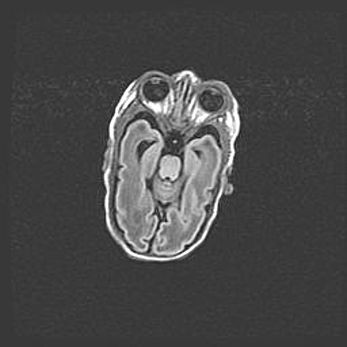

Церебральная ишемия II.

Возраст: 5 дней

Вес: 3400 г

Пол: женский

Окружность головы: 35 см

Срок гестации: 39 недель

Церебральная ишемия – это заболевание, характеризующееся недостаточностью (гипоксией) либо полным прекращением (аноксией) снабжения мозга кислородом по причине закупорки одного или нескольких сосудов. Это приводит к  что метаболическим расстройствам различной степени тяжести в тканях головного мозга, развитию коагуляционных некрозов и гибели нейронов.